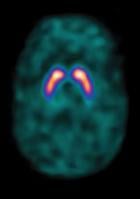

A normal brain scan with the SPECT imaging agent DaTscan showing normal dopamine transporter (DaT) activity.

GE Healthcare’s DaTscan (ioflupane I 123 Injection) is the first FDA-approved diagnostic imaging agent to help physicians evaluate neurodegenerative movement disorders, such as idiopathic (of unknown cause) Parkinson's disease (PD). DaTscan may be used as an adjunct to other diagnostic evaluations to help differentiate essential tremor from tremor due to PS. DaTscan cannot differentiate between the different types of PS.

The FDA's action, following a priority review, marks the approval of the first radiopharmaceutical agent to detect DaT distribution within the brain (dopamine is a brain chemical that is classified as a neurotransmitter and is found in regions of the brain that regulate activities such as movement and emotion(2)). The FDA granted DaTscan priority review due to an unmet clinical need for an imaging agent to assist physicians in managing patients according to their dopaminergic status.

The FDA's approval of DaTscan was based on two phase 3 clinical trials confirming the efficacy of DaTscan for the visualization of DaT distribution within the striata, an interior part of the brain. These studies, evaluating 284 adult patients with tremor, demonstrated the consistent performance of DaTscan in the visual detection of DaT distribution in the brain when compared with a reference clinical diagnosis.(1)